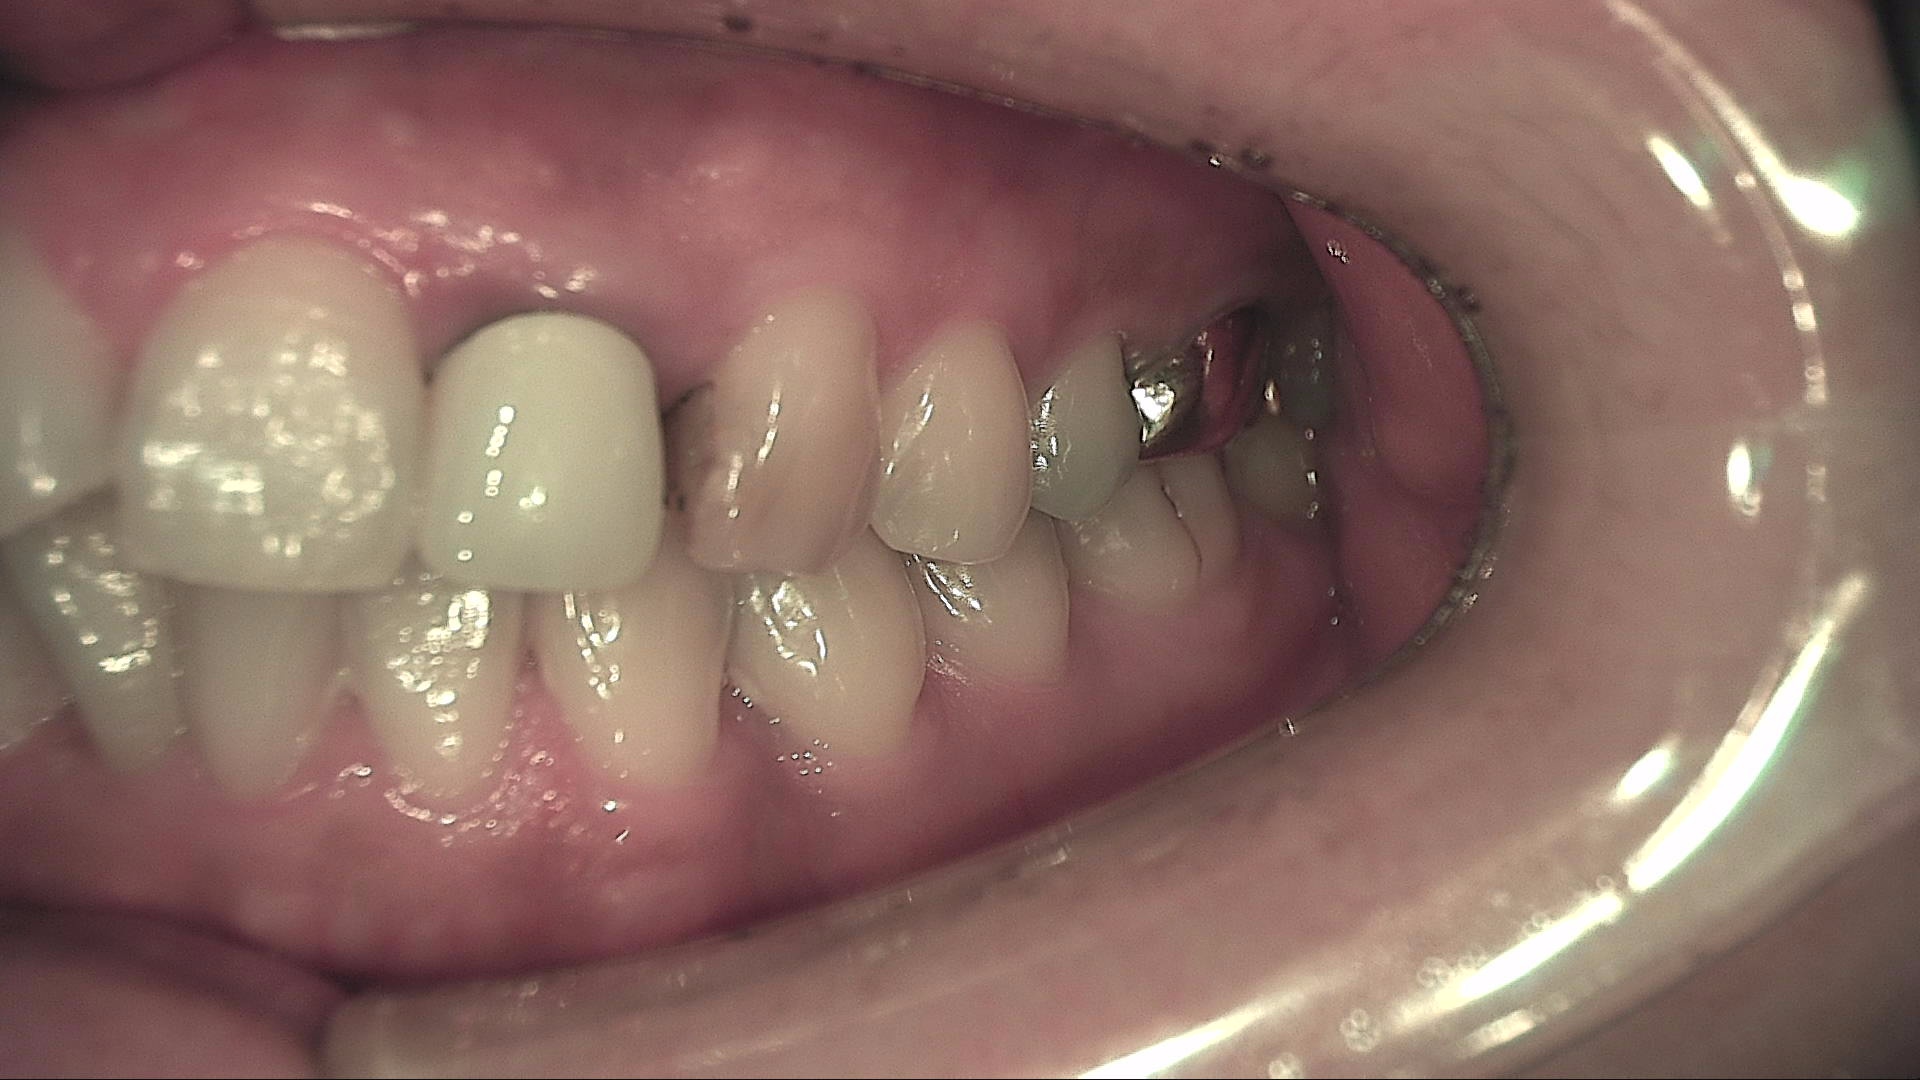

BEFORE & AFTER

일반진료